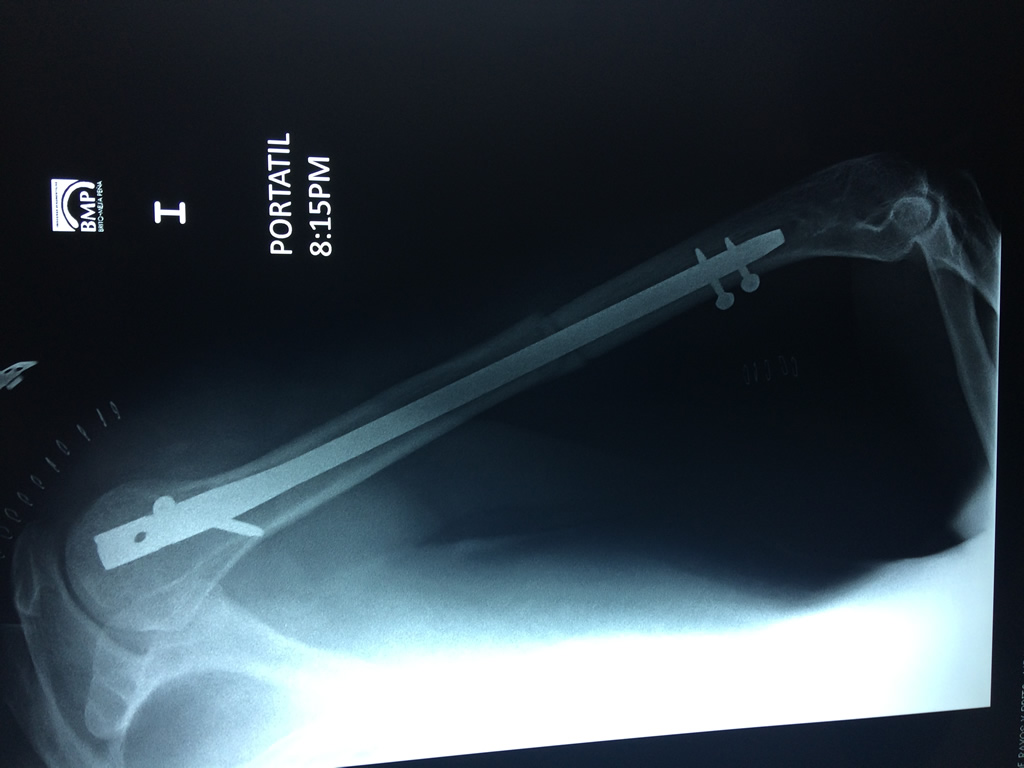

humeroEl Húmero (en latín, humerus) es el hueso más largo de las extremidades superiores en el ser humano. ​ Forma parte del esqueleto apendicular superior y está ubicado en la región del brazo. ... El extremo proximal del húmero tiene la cabeza, cuellos quirúrgico y anatómico y tubérculos mayor y menor.

Húmero